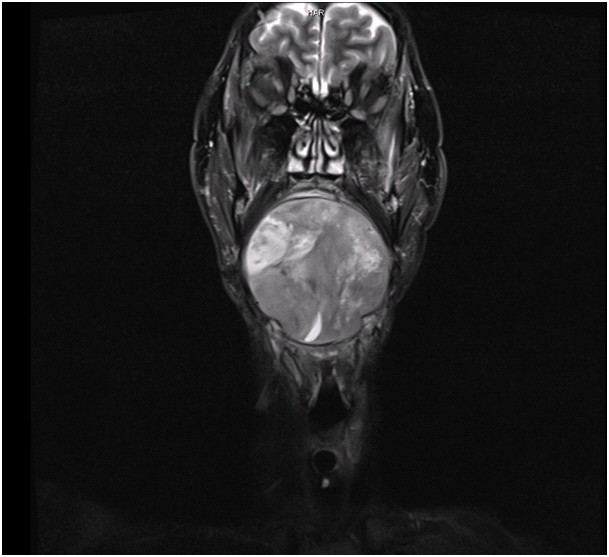

Rhabdomyosarcoma (orbit) | Radiology Reference Article | Radiopaedia.org

radiopaedia.org

radiopaedia.org

www.sciencephoto.com

www.sciencephoto.com

rhabdomyosarcoma mri

MRI Of Rhabdomyosarcoma And Other Soft-Tissue Sarcomas In Children

pubs.rsna.org

pubs.rsna.org

rhabdomyosarcoma mri tissue sarcomas